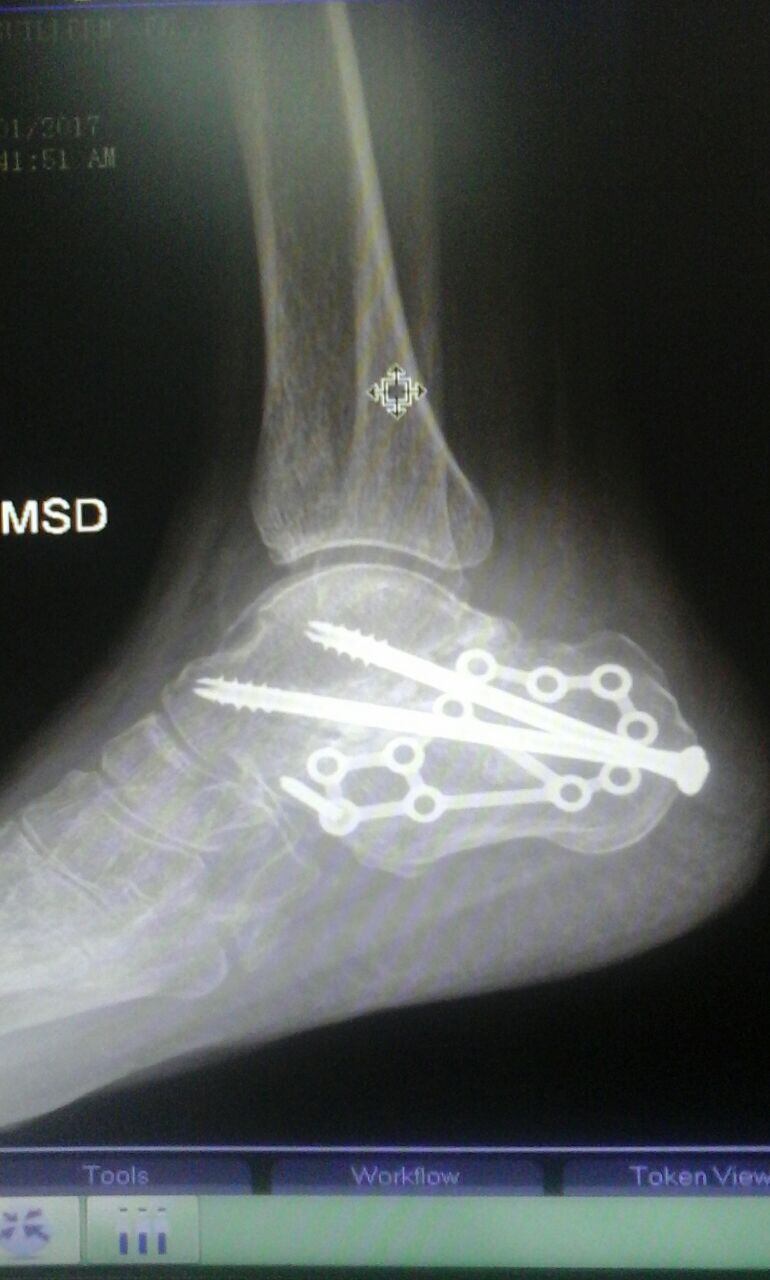

Aunque en el hospital le dijeron que sufrió una fisura don Enrique sabía que no era así, pues estaba hinchado y casi negro, según contó. Al ser evaluado en el INS se enteró que lo que tenía era una grave lesión en los huesos que forman el talón.

Desde ese día don Enrique ha tenido que ser operado en tres ocasiones, pero ninguna de las intervenciones le ha ayudado a reducir el dolor, especialmente por las noches, cuando a veces se pone a llorar y no solo por el dolor, sino también por la frustración que siente.